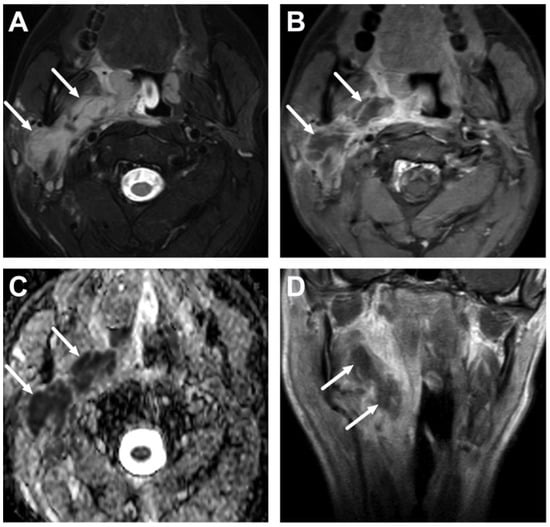

5.1. Lymphadenitis with Purulence vs. Necrosis